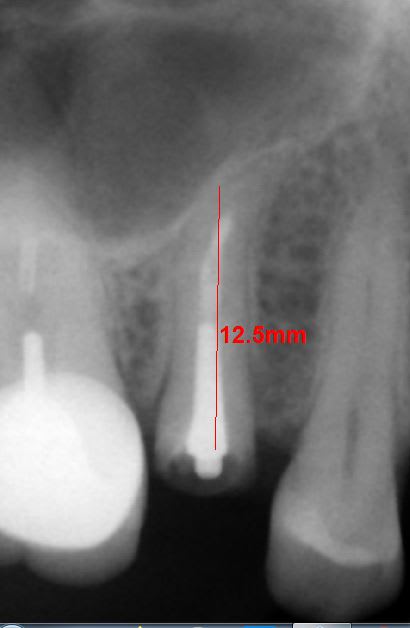

Que feriez vous dans cette situation,avec cette racine contre le plancher sinusien ? Est ce que une Extraction implantation immédiate est envisageable sans faire de sinus lift ? La patiente n'en veut pas.

Comment obtenir une stabilité ...en se mettant contre la paroi palatine ? Ou extraire et attendre 6 à 8 semaines

12.5 c'est au cbct?

perso je regarde la forme de l'avéole vers le 1/3 apical et je trouve un 10 ou un 12 qui bloque.

Non c'est la mesure prise sur la rétro. ..Mais tu vois que l'apex est courbé ..oui au scan ce doit être normalement plus précis ...mais en venant bien contre la paroi du plancher c'est pas toujours sûr d'avoir une tenue ...des fois ça bouge 2 semaines après et obligé de déposer

...le mieux c'est d'avoir 3 mm d'os au delà de l'apex pour se fixer..